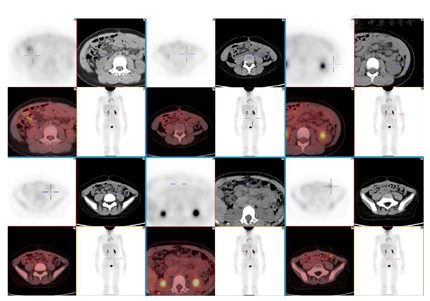

入院前复查肿瘤标记物及性激素六项、AMH均在参考值范围内。2022年4月10日MRI:左侧腰大肌前方3枚结节,直径约8 mm,转移可能。腹部散在结节影,肿瘤腹膜转移可能,肠系膜根部散在小淋巴结。4月26日PET/CT:胃窦下方、左肾前方、脾下方、右上腹肠系膜上、左腰大肌前方、左中腹大网膜上多发转移灶,较大者约1.2 cm×0.8 cm(图1)。其余血常规、肝肾功能、尿常规、凝血、血型、输血8项及心电图等术前检查、检验基本正常。